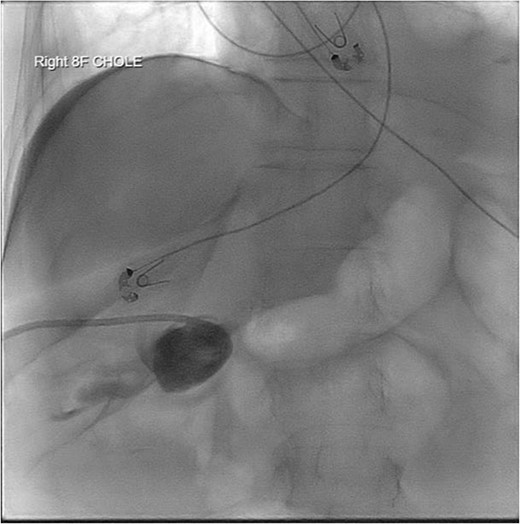

PCT check using fluoroscopy showing retracted tube in the peritoneal fluid.

Five days post-PCT replacement, the drainage became a white thick consistency, with an output of 1200 milliliters (ml) in 24 hours. The triglyceride level of the fluid was 683 mg/dL, consistent with chylous output. After transitioning to parental nutrition, her output decreased to 700 ml in 24 hours. However, this was short-lived and outputs increased to 800–1000 ml per day.

Repeat imaging was performed and revealed peri-hepatic ascites, significant anasarca and bilateral pleural effusions (Fig. 3) while the PCT remained in good position (Fig. 4). Bilateral chest tube placement and drainage of the pleural effusions revealed chylothorax and malignant cells. Cultures of both PCT output at the time of insertion and pleural fluid cultures grew no organisms.

PCT check using fluoroscopy showing the pigtail portion of the cholecystostomy tube within the gallbladder lumen as well as some leakage into the perihepatic space. No opacification of the pleural space.